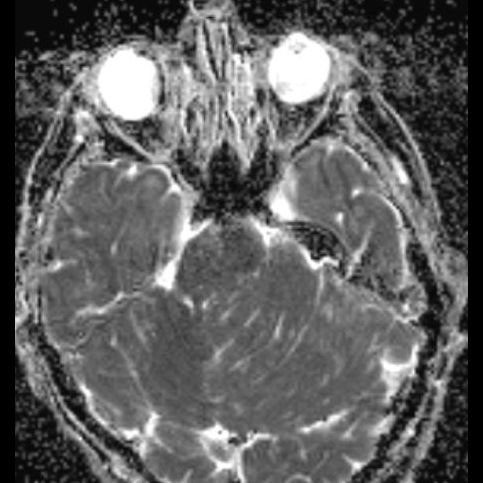

24 yaş, E

Baş ağrısı

Lhermitte-Duclos hastalığı (Dysplastic cerebellar gangliocytoma)